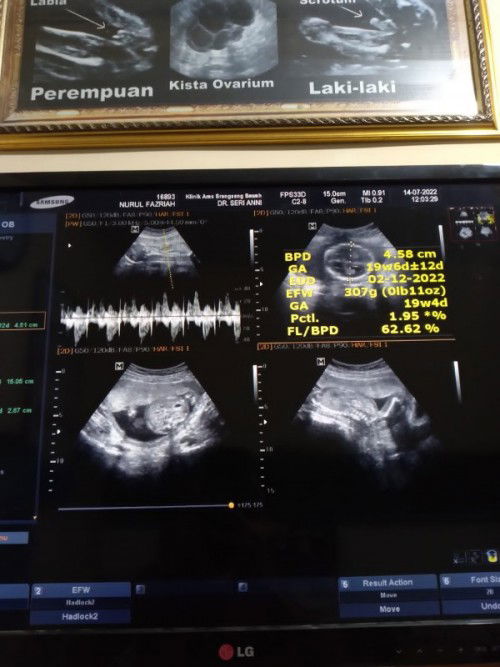

Hari ini abis usg, hpht 15-18 feb 2022 Di aplikasi baru masuk 18 minggu, usg 19 minggu6day, baru mau 4 bulanan, ini udah 5 bulan jalan, hpl nya juga berubah2...jd bingung sendiri ygmana yg akurat Ikutin hpht hpl nya 20 nov 2022 Ikutin usg pertama pas 5 week 9/12/22 Ikutin aplikasi ini 12/12/22 Ikutin usg hari ini 19 weeks 2/12/22